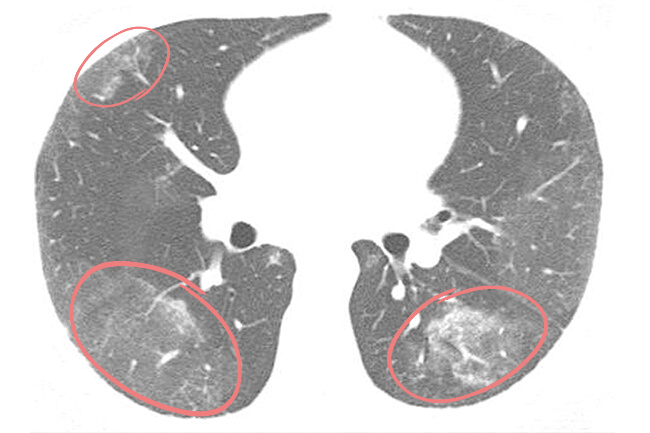

Фотографии, демонстрирующие обнаруженное усиление легочного рисунка

Раздел: Фотодневник открытий